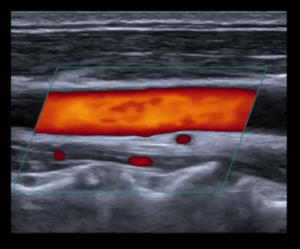

At Concierge Cardiology of MT, we firmly believe patients of all ages should have access to various options for heart screening. That’s why we offer heart screening services, including consultations, electrocardiograms (ECGs/EKGs), and echocardiograms (heart ultrasound). Dr. Hua, our experienced cardiologist, is passionate about providing the best care possible to our patients.